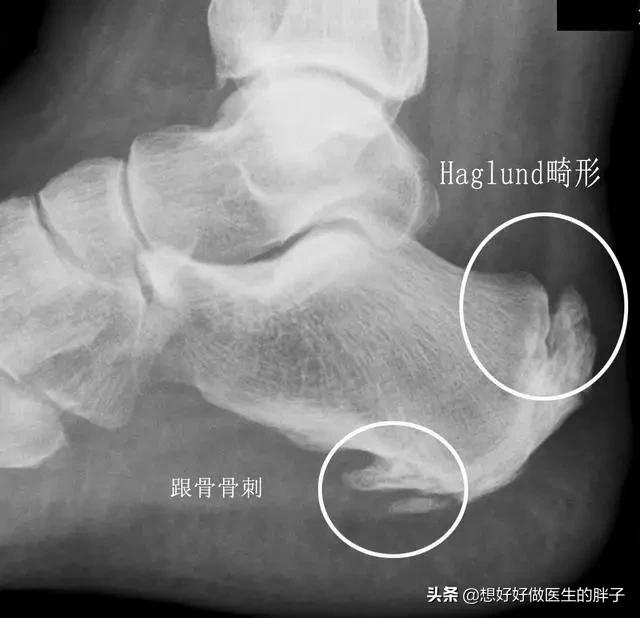

第三,还有一些骨刺,虽然不会影响患者的活动范围,也不会造成神经的卡压,但是会造成患者活动性的疼痛,就是说只要一活动就会疼痛。比如跟骨骨刺,虽然不是占全部的因素,只占30%左右,但是确实有着一部分患者是因为骨刺导致的活动性疼痛。#清风计划# #青云计划#